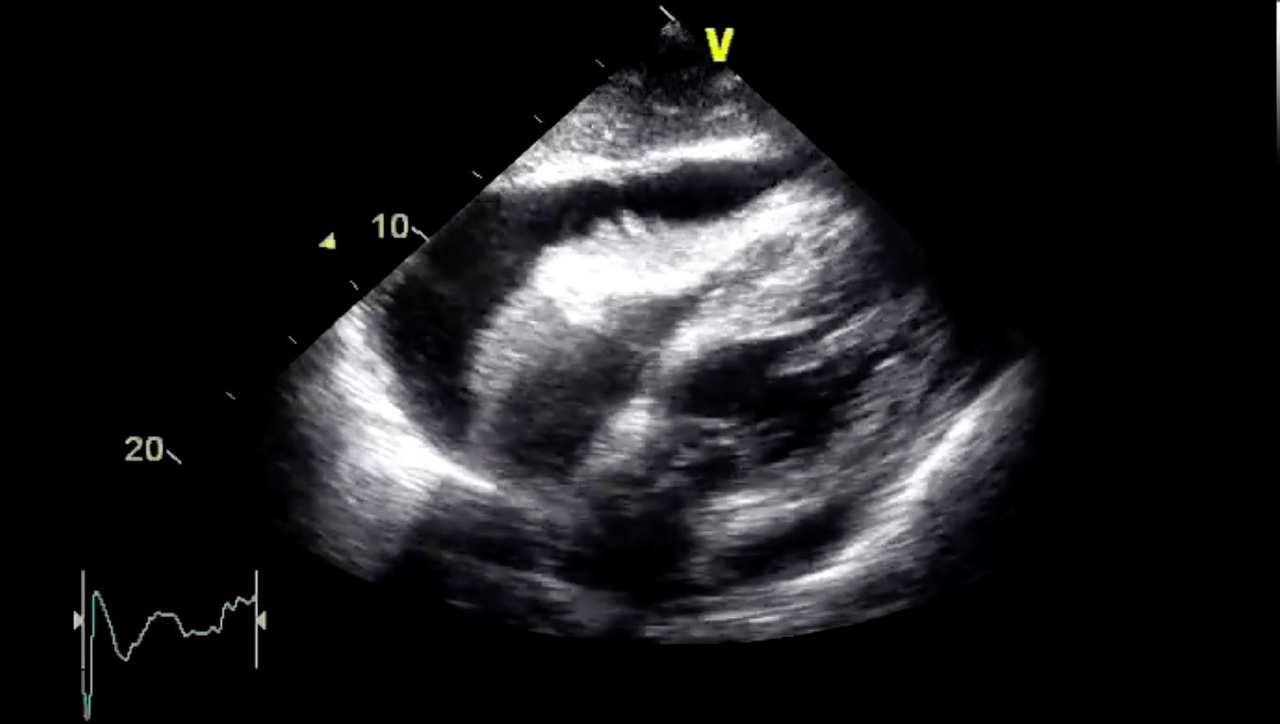

Voici la coupe sous-costale de l’échographie cardiaque que vous réalisez en urgence (figure 5). La valve mitrale est normo-fonctionnelle. Le ventricule droit est modérément dilaté. Les pressions artérielles pulmonaires systoliques sont normales, estimées à 30 mmHg. La pression de l’oreillette droite est augmentée, estimée à 20 mmHg, avec une veine cave inférieure dilatée et non compliante. Vous observez une variation des flux mitraux et aortiques avec la respiration. Le débit cardiaque est abaissé.

Il s’agit ici d’une tamponnade. Il n’y a pas de cœur pulmonaire aigu

Prise en charge d’une tamponnade :